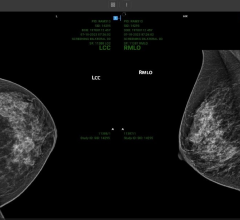

Despite decades of progress in breast imaging, one challenge continues to test even the most skilled radiologists ...

According to a study published in Radiology, a journal of the Radiological Society of North America, the newer, 3D form ...